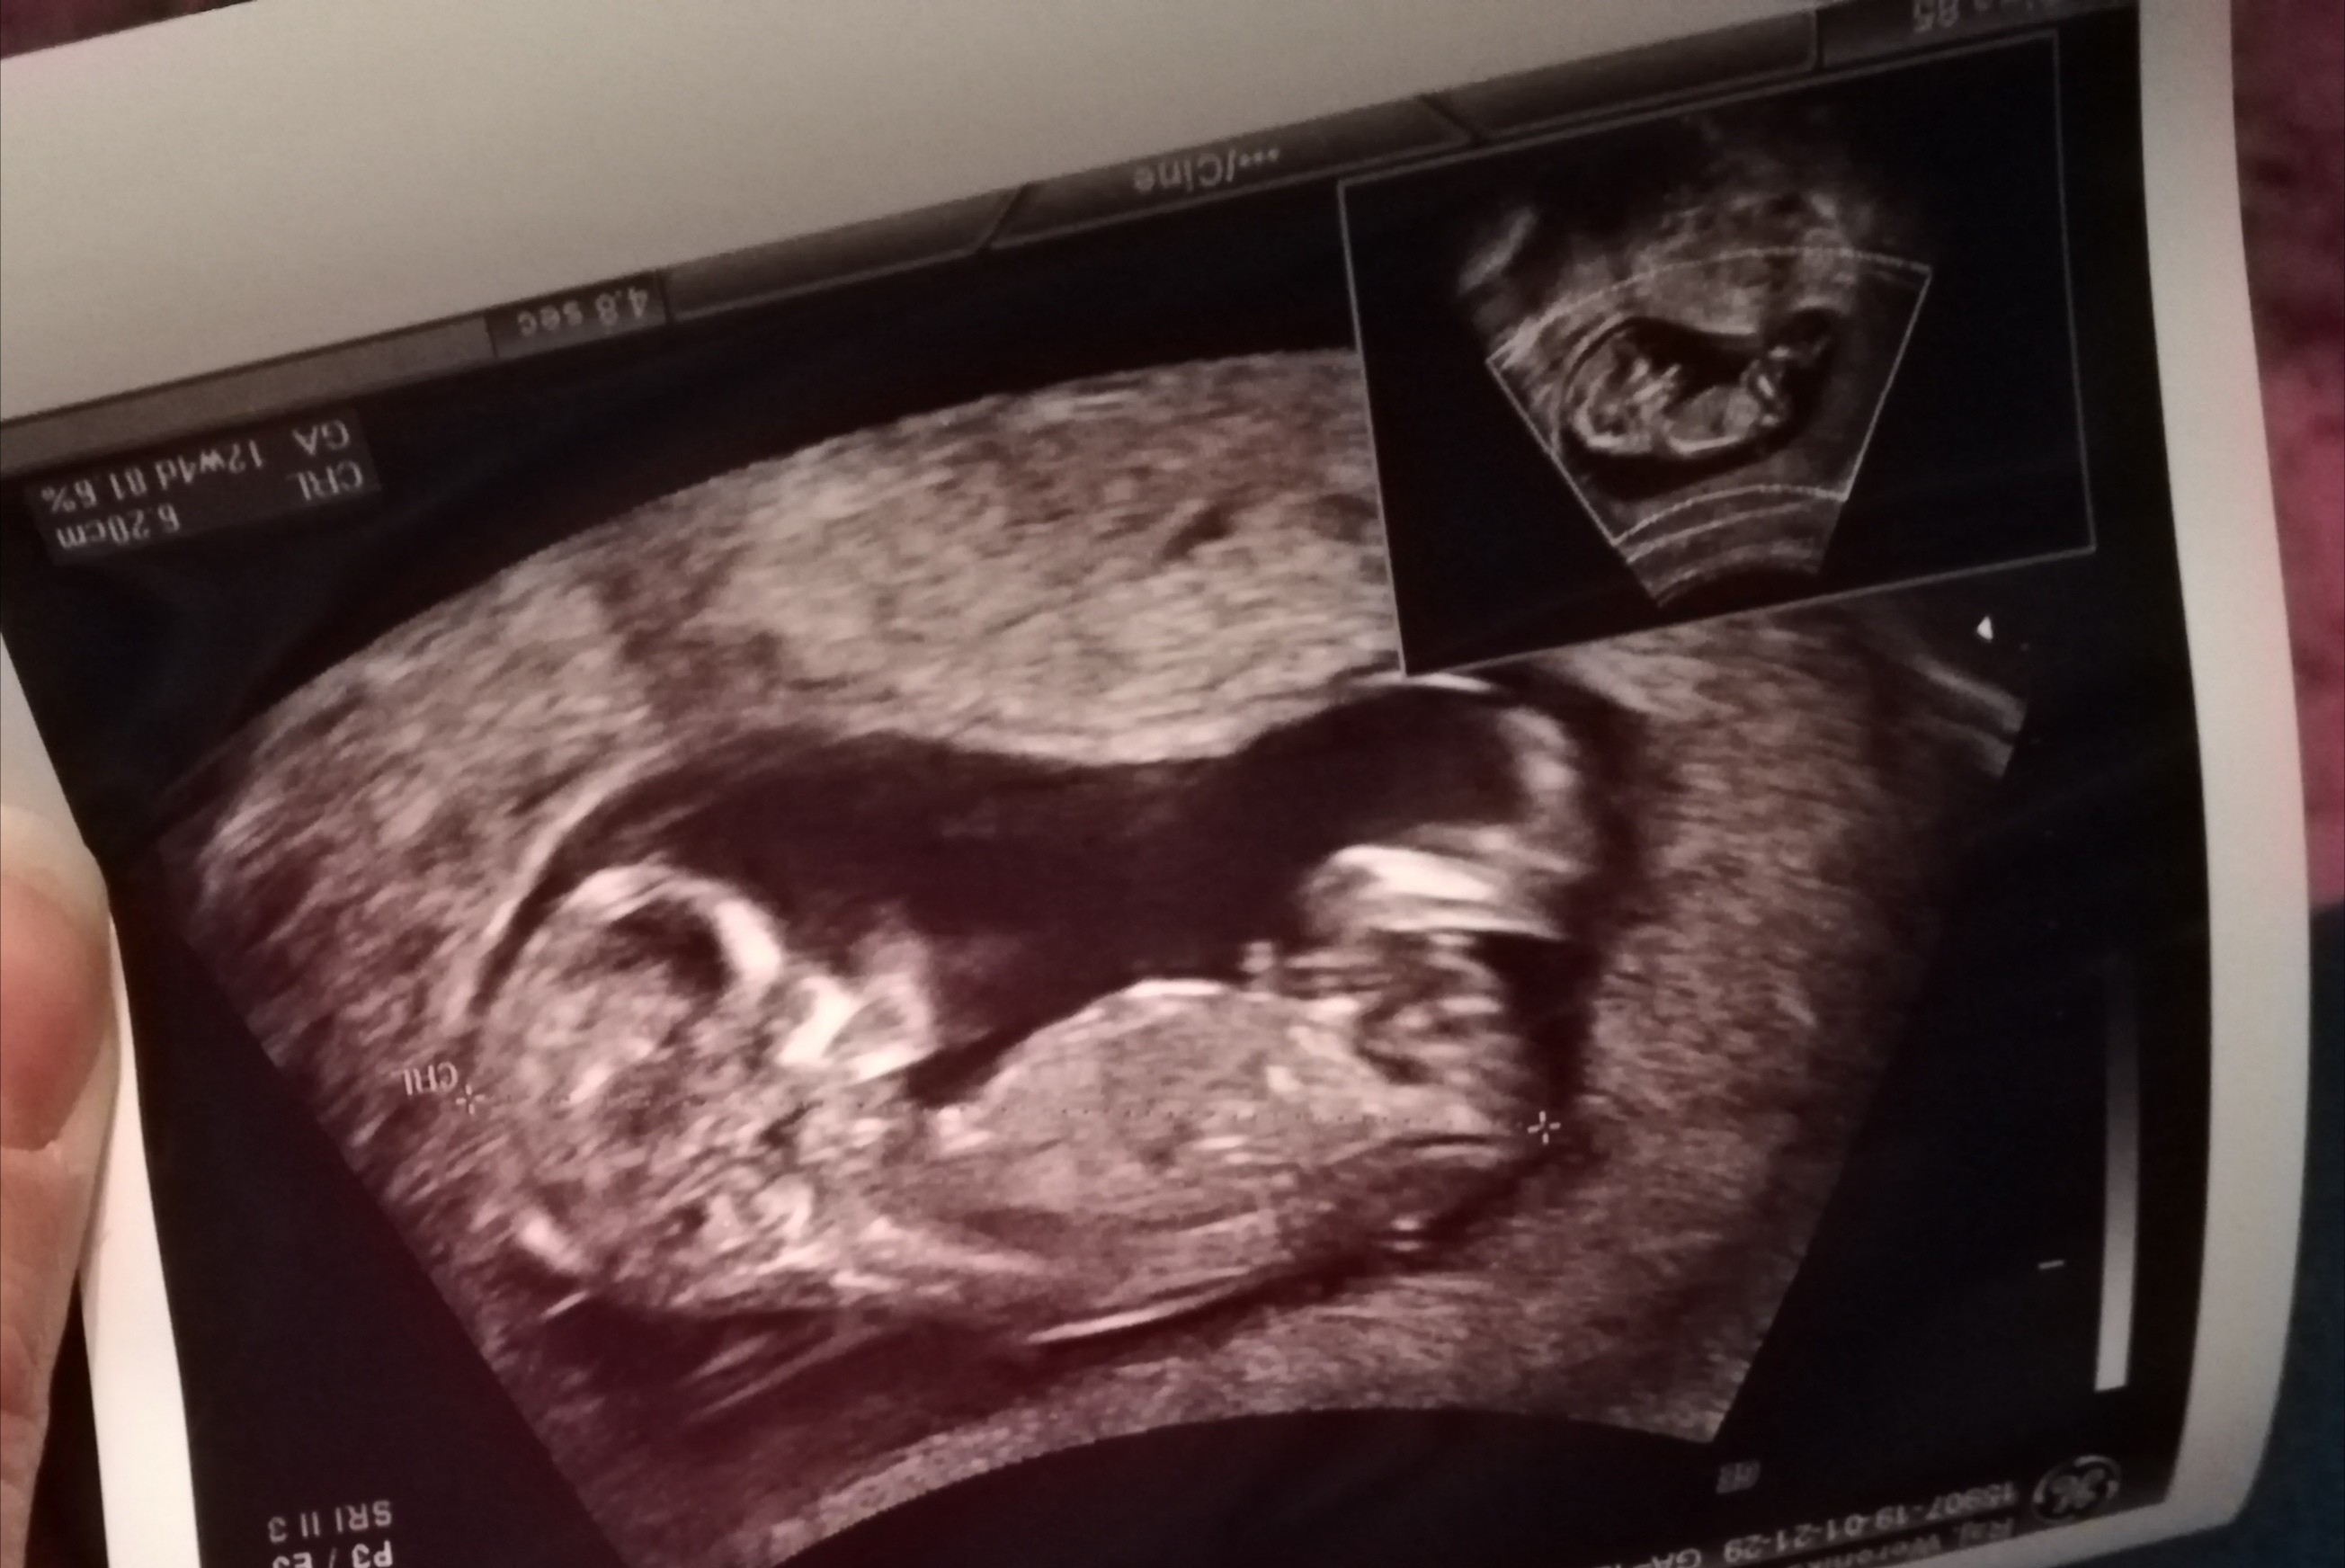

Hej dziewczyny :) jestem tu nowa. Termin porodu na 3 sierpnia :) to mija druga ciąża, w domu 7 letnia córa, teraz jak narazie płeć nieznana. Czy z tego zdjęcia można by się pokusić o rozpoznanie płci? :) jak myślicie? Z góry dziękuję

IMG_20190215_204416.jpg